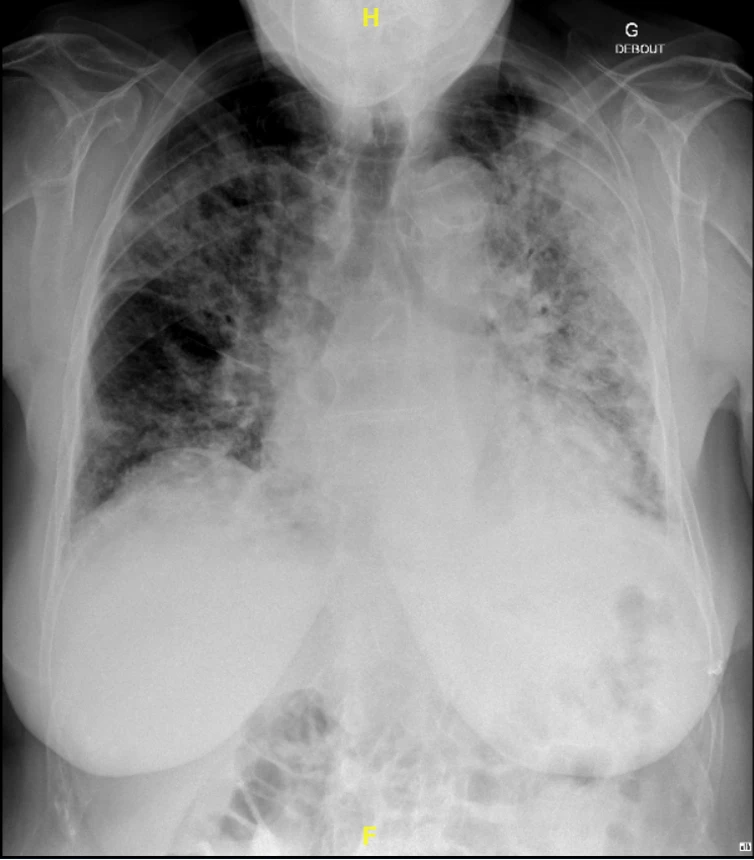

Madame Y est une patiente de 63 ans se présentant aux urgences pour dyspnée, toux et baisse de l’état général. L’examen clinique met en évidence une désaturation importante. La radiographie du thorax révèle un infiltrat alvéolaire panlobaire gauche avec un bronchogramme aérique. Les antigènes urinaires sont positifs pour une légionnelle. Face à un syndrome de détresse respiratoire aigu la patiente est intubée. Son évolution est favorable sous Levofloxacine.